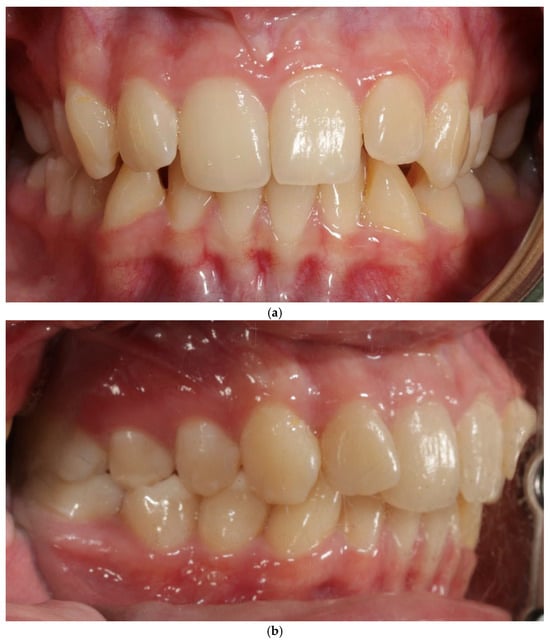

A 27-year-old female patient presented with a thin periodontal phenotype based on probe-transparency test, mild crowding in both arches, and narrow alveolar anatomy confirmed clinically and radiographically—Figure 1a–c. Thin phenotypes are known to present a significantly increased risk of buccal bone loss during expansion, especially when the cortical plate is critically thin at baseline [1,24,25,26].

Figure 1.

Patient 1—before treatment (a–c).

A 22-year-old female patient presented with: anterior open bite, maxillary constriction, crowding and a thin periodontal phenotype—Figure 3a–c.

Figure 3.

Patient 2 before treatment (a–c).